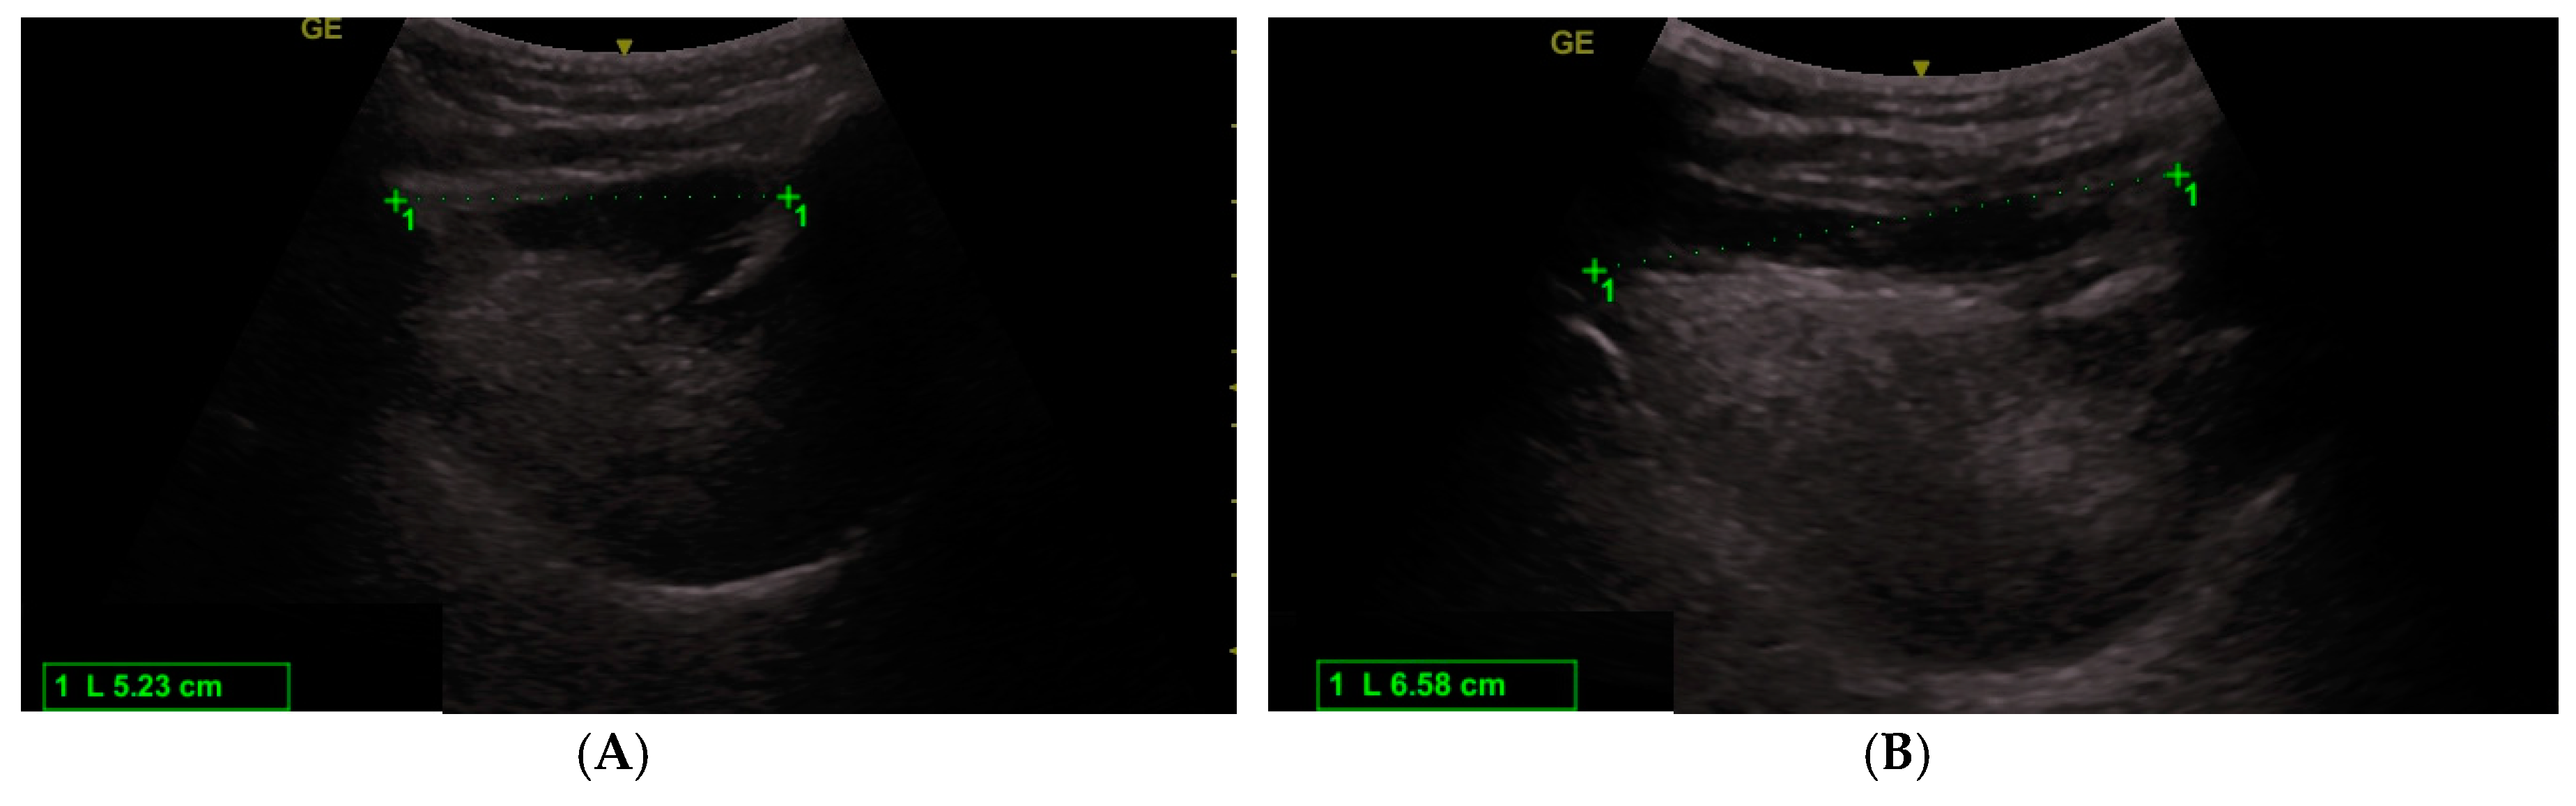

| HMDecho neutral | 4.16 ± 0.49 | 4.75 ± 0.47 | 0.54 |

| HMDecho extended | 5.23 ± 0.59 | 5.71 ± 0.63 | 0.0036 |

| HMDRecho | 1.26 ± 0.16 | 1.20 ± 0.07 | 0.00314 |